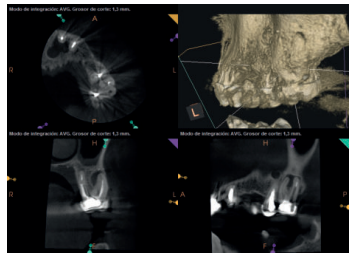

Para confirmar el origen endodóntico y el tamaño de las lesiones se realizaron exploraciones tomográficas con espesor de corte de 75 micras mediante CBCT CS8100 (Carestream Dental® ) en las que se evidenciaron lesiones periapicales radiolúcidas a nivel de 12, 11, 21 (con afectación bicortical), 25 y raíces vestibulares de 26 (Figuras 4 a 8).